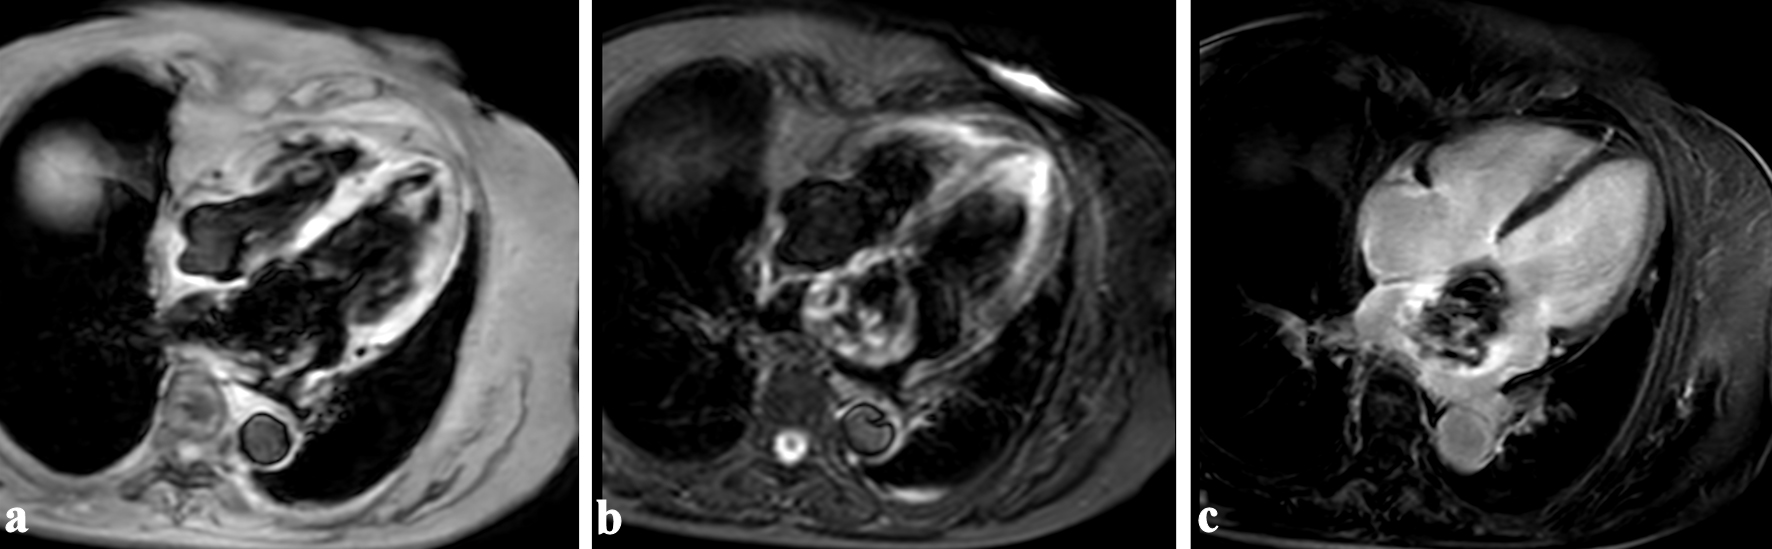

Transthoracic echocardiography showed a large (37 × 39 mm), well-defined, oval-shaped, heterogenous mass in a dilated left atrium (45 mm) (Fig. 1a). Transesophageal echocardiography confirmed that the mass was sessile and immobile with a wide septal attachment (Fig. 1b). Moderate mitral regurgitation associated with annular dilatation was observed (Fig. 1c). No mass was found in the left atrial appendage, and head magnetic resonance imaging showed no embolization.

Figure 1. Transthoracic (a) and transesophageal echocardiography (b) showed a large mass (white arrows) in a dilated left atrium. The mass was attached to the interatrial septum with a wide base. Moderate mitral regurgitation associated with annular dilatation was observed (c). LV: left ventricle; RA: right atrium.